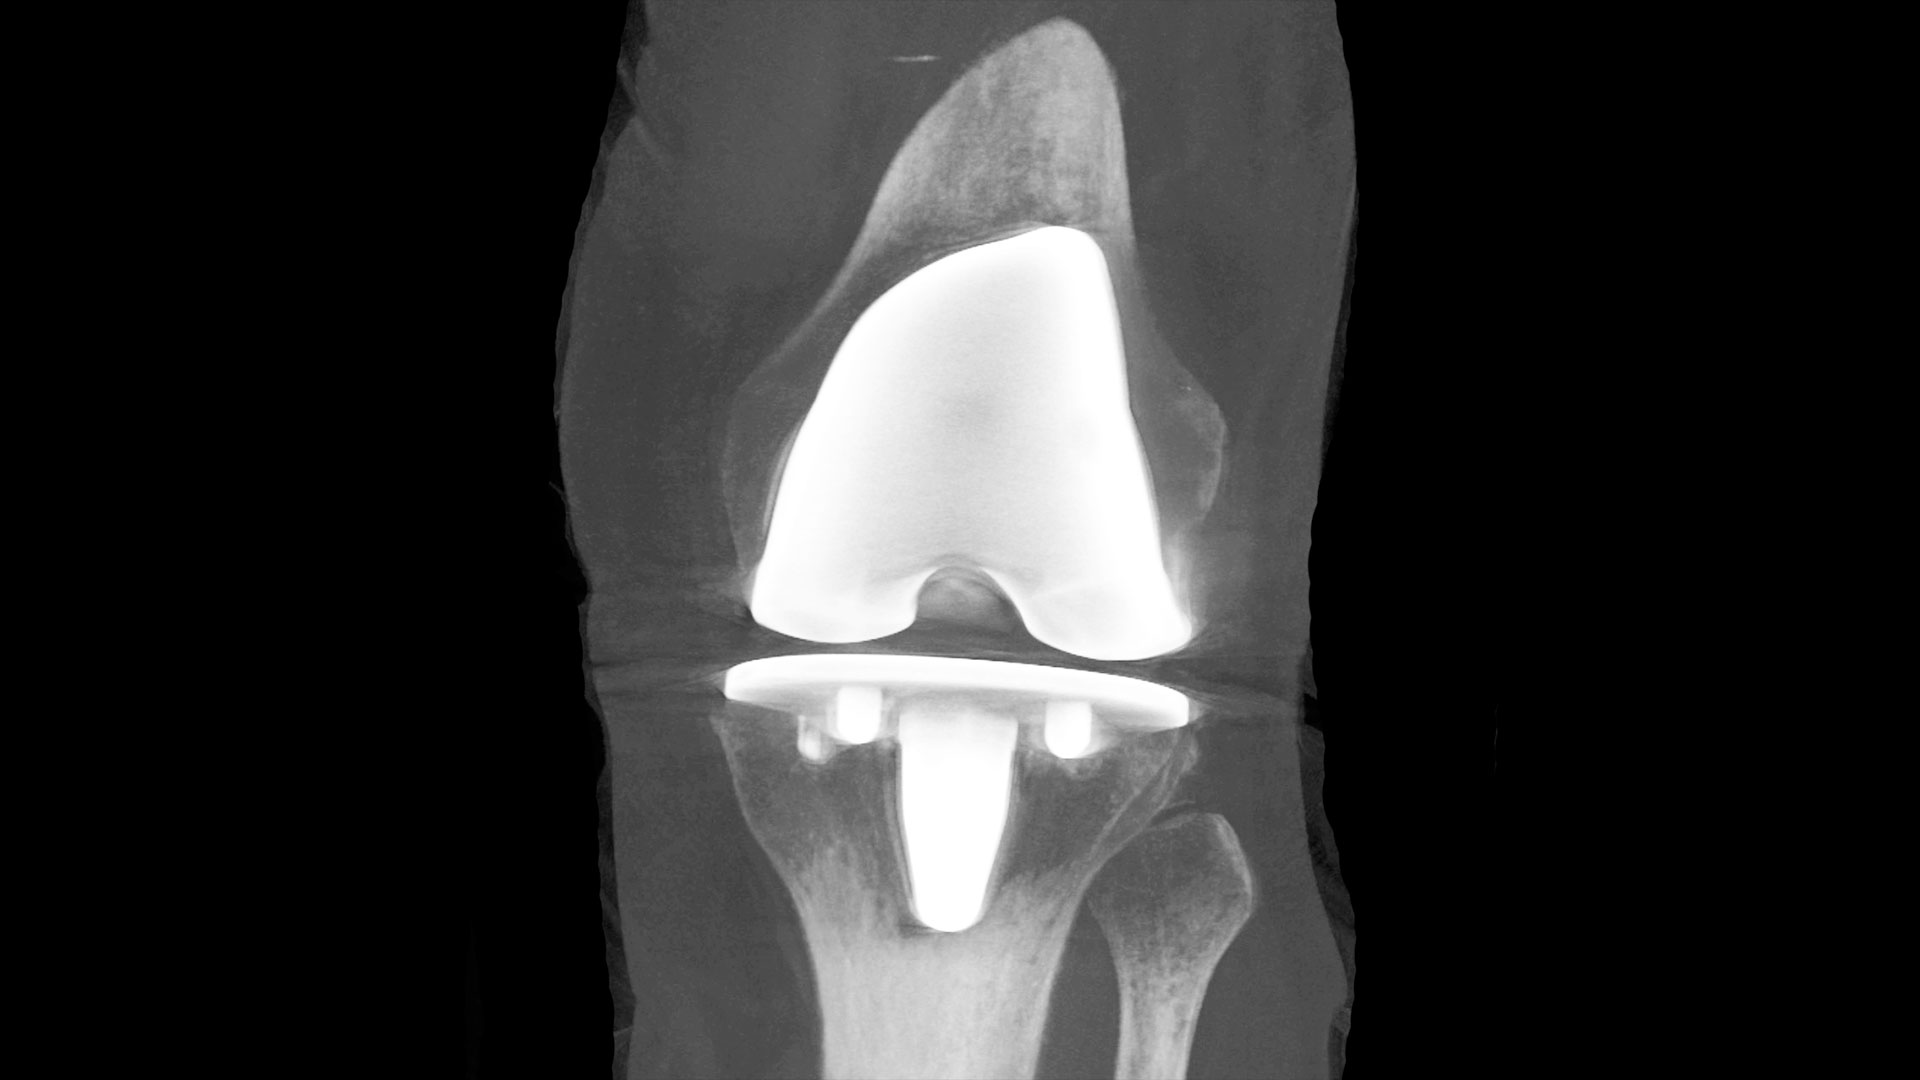

12. New study examining if probiotics can improve outcomes in knee replacement surgeries

Lawson researchers launched a study to assess whether daily probiotics can improve outcomes in patients undergoing a total knee replacement surgery. Of the more than 70,000 knee replacement surgeries in Canada each year, nearly 10 per cent of patients experience complications. With patients who are considered healthy likely to have better outcomes, the research team is interested in improving the gut microbiome as a way to support patients’ overall health. Read more.